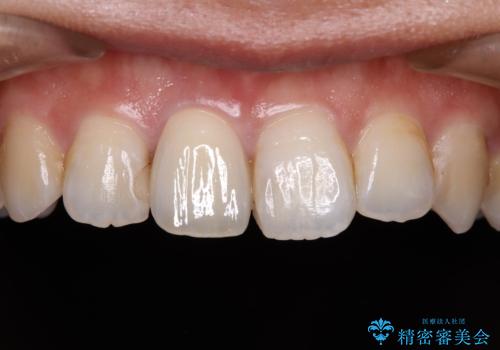

不自然な前歯の被せものをやり替えたい

- 数年前に他院で治療した右上の前歯の色が不自然なことを主訴として来院された患者様です。

隣在歯と色、形ともに合っていません。

また、被せものと土台の境目が歯肉よりも上に見えていて、段差になっています。

そのため審美性、清掃性どちらの観点からもあまりよくない状態です。

色、形ともに自然で嬉しいですと笑顔で言っていただけました。